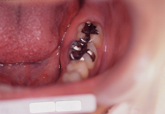

セラミックインレー

セラミックインレーとは、奥歯などのむし歯の治療部位に金属ではなく、

残っているご自分の歯と同じ色のつめ物を入れます。

素材は全てセラミックで出来ているので、色の変化もなく見た目も白く

虫歯で削った部分なのに口を大きくあけて笑っても目立つことなく

とても清潔感を与えてくれます

金属アレルギーの心配もありません。

術前                     術後